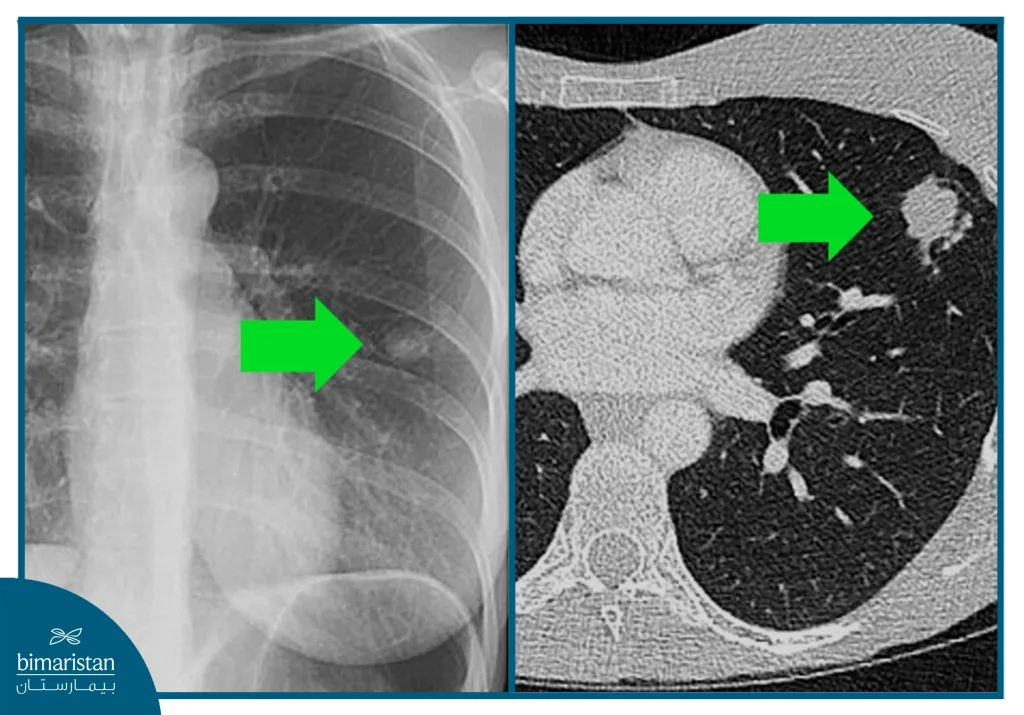

تلعب الفحوص الشعاعية دوراً محورياً في تشخيص مرض السل، إذ تساعد على تقييم مدى تأثر الرئتين أو الأعضاء الأخرى وتحديد مرحلة الإصابة، وعلى الرغم من أن الفحص المخبري هو الذي يؤكد التشخيص نهائياً، إلا أنّ التصوير يُعدّ أداة مهمة لتوجيه الطبيب ومتابعة تطور الحالة. تشمل أبرز الفحوصات:

- الأشعة السينية للصدر: تُستخدم كفحص أولي لتقييم الرئتين، إذ قد تُظهر التجاويف، أو التليف، أو التكلسات المميزة لعدوى السل، لكنها لا تكفي وحدها لتأكيد التشخيص.

- الأشعة المقطعية: تُظهر تفاصيل أدق من الأشعة السينية وتساعد في اكتشاف الآفات الصغيرة أو التجاويف العميقة، وتفيد في تقييم مدى انتشار العدوى داخل الصدر.